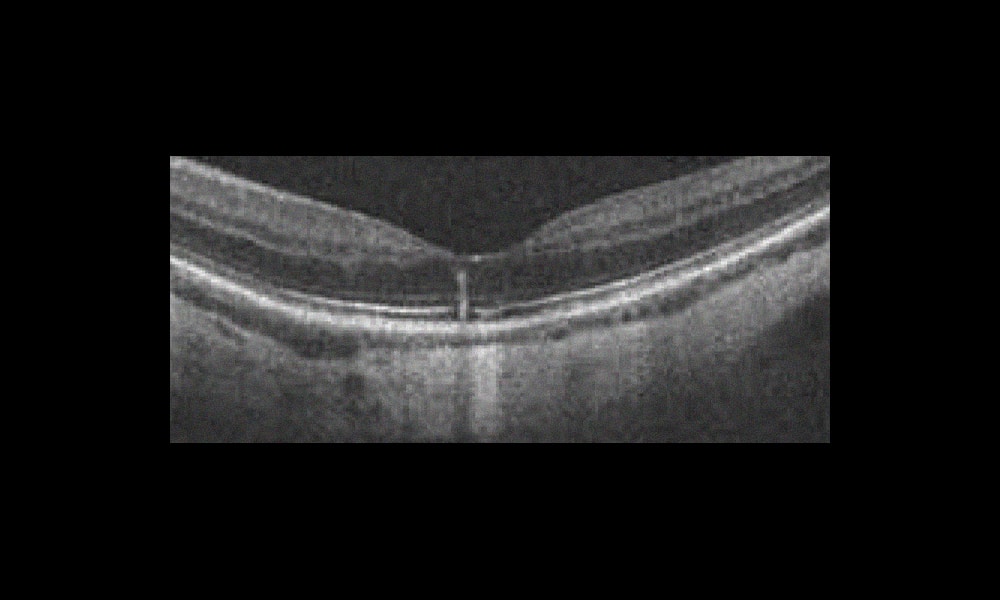

Des lignes hyperréflective rétiniennes verticales (38 yeux) ou curvilignes le long de la couche de fibres de Henle (11 yeux) ont été observées en association avec des affections maculaires diverses : dystrophie pseudovitelliforme de l’adulte ou dystrophie maculaire réticulée (24 yeux) fréquemment associée à une membrane épirétinienne (6 yeux) et/ou une choroïde épaisse (9 yeux), maculopathie liée à l’âge (MLA) ou DMLA (9 yeux), résorption partielle d’hémorragies sous-rétiniennes ou intrarétiniennes (5 yeux), micro-trou maculaire (2 yeux), traction vitréo-maculaire (3 yeux), syndrome des points blancs multiples évanescents (MEWDS) (3 yeux), fundus flavimaculatus (2 yeux) et épithéliopathie pigmentaire avec pachychoroïde (1 œil, fig. 1). Les lignes disparaissent complètement dans les cas d’hémorragies, de syndrome des points blancs multiples évanescents ou de résolution de la traction vitréo-maculaire mais, dans les autres cas, elles persistent généralement avec un amincissement progressif de la rétine.

L’article illustre la variété des pathologies pouvant être[...]